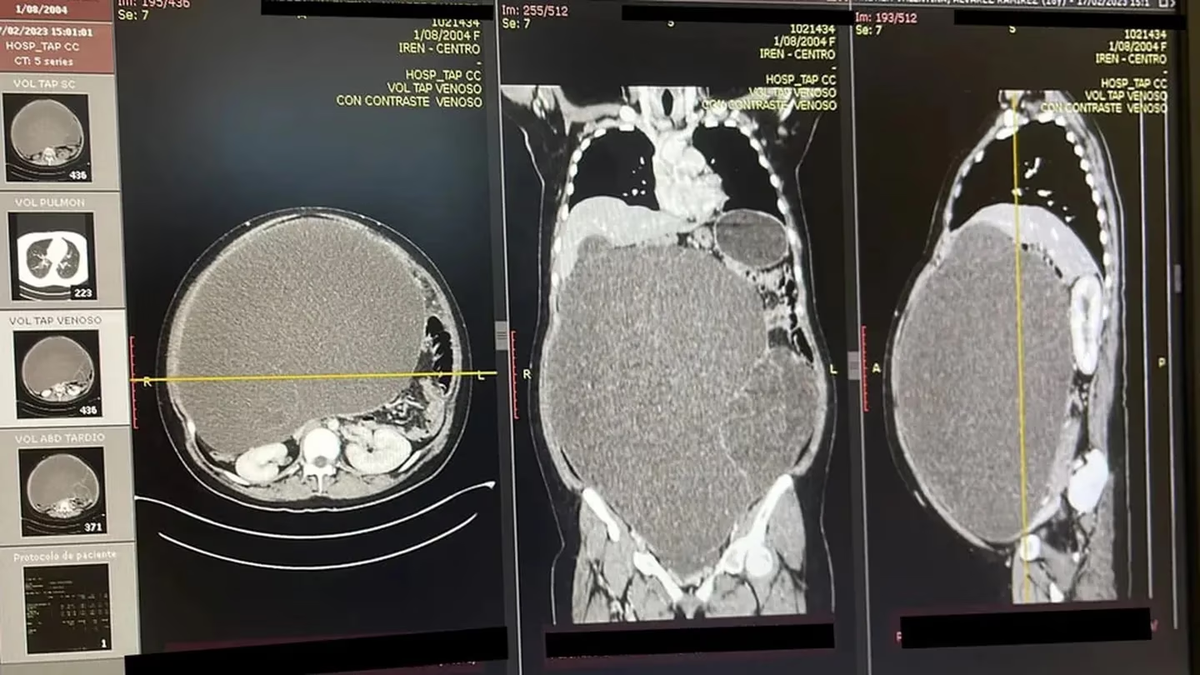

Hasta entonces, tanto la paciente como su familia creían que el bulto de su estómago era debido a la obesidad y no a un tumor. Para tener una noción del tamaño del abdomen de Álvarez, los médicos lo compararon con una panza embarazada de gemelos.

El médico que encabezó la operación de Álvarez es Danilo Baltazar. Luego de la cirugía, él se refirió al proceso: “Con éxito, se extrajo la tumoración abdominopélvica gigante con áreas quísticas y sólidas y se envió una muestra a estudios patológicos”.